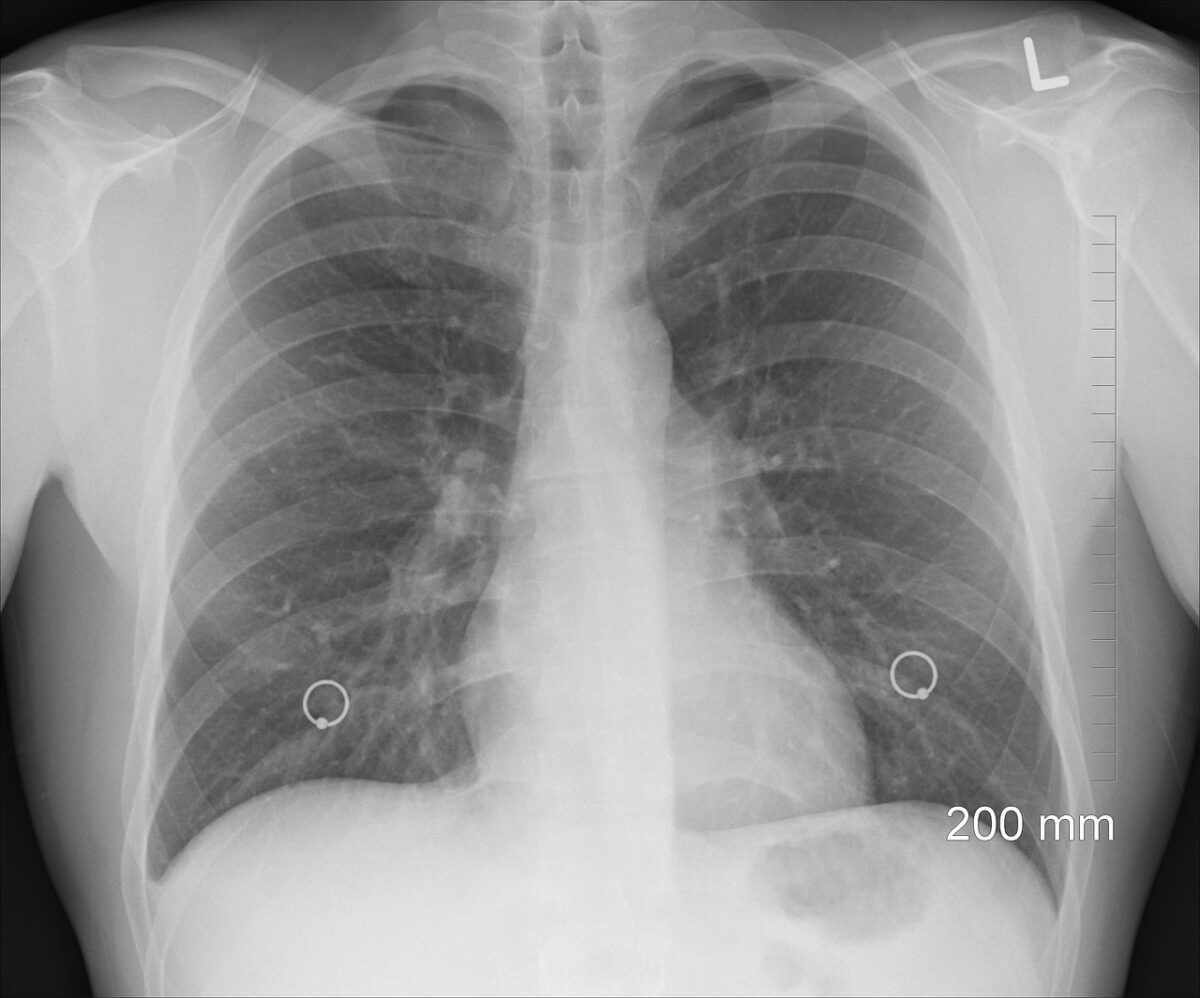

Indennità per malattia tubercolare: l’Istituto Nazionale di Previdenza Sociale mette a disposizione all’interno del proprio sito web ufficiale un apposito servizio online attraverso il quale consente ai soggetti interessati di presentare la domanda per beneficiare di un'indennità che viene riconosciuta durante il corso di tutto il periodo relativo allo svolgimento delle cure ospedaliere o ambulatoriali.

Tale prestazione economica, in particolare, viene riconosciuta durante tutto il periodo in cui vengono effettuate le cure ospedaliere o ambulatoriali/domiciliari, esclusivamente nel caso in cui il lavoratore interessato non abbia il diritto di beneficiare dell'intera retribuzione a lui spettante.

A tal proposito, pertanto, l'indennità in oggetto decorre dal giorno in cui ha inizio la malattia tubercolare, anche qualora quest'ultima sia stata certificata all'inizio come malattia comune, ed ha una durata pari a tutto il periodo in cui avviene la cura fino alla data di stabilizzazione o di guarigione del lavoratore beneficiario.